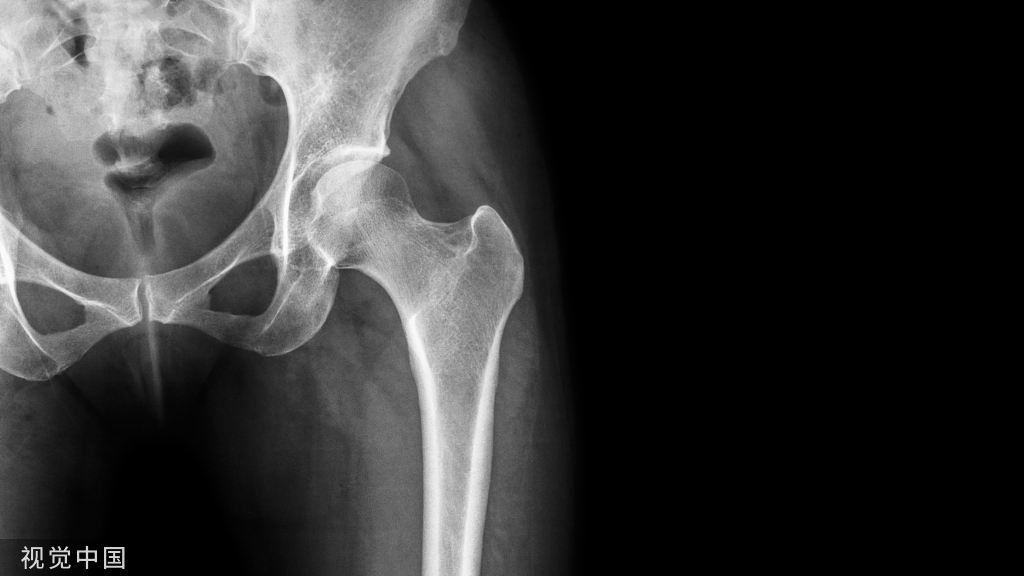

相对于传统融合术,Wallis动态稳定系统作为全新的一种手术方式被提出用于治疗腰椎退行性疾病。目前国内外已有众多研究表明Wallis动态稳定系统比传统融合术,缩短了手术时间,减少了术中出血、住院天数及并发症的发生,并在早中期研究中显示出了相同的临床效果。此外,在生物学和影像学方面,该系统在术后早中期能有效地保留腰椎活动度、保持腰椎稳定及延缓邻近节段退变。在最新研究中该系统可以减缓邻近节段退变,但是对不同程度的退变,如何能够更好地预防退变也没有统一标准。对于腰椎术后腰椎间盘再水化,目前国内外研究相对较少,无论是动物实验还是人类研究,均发现椎间盘具有再水化的能力,并没有明确Wallis动态稳定系统MRI上信号的改变是椎间盘水肿还是髓核组织再生导致。但是,Wallis动态稳定系统毕竟是一种新的外科技术,其适应证、远期临床疗效及并发症需要进一步研究。